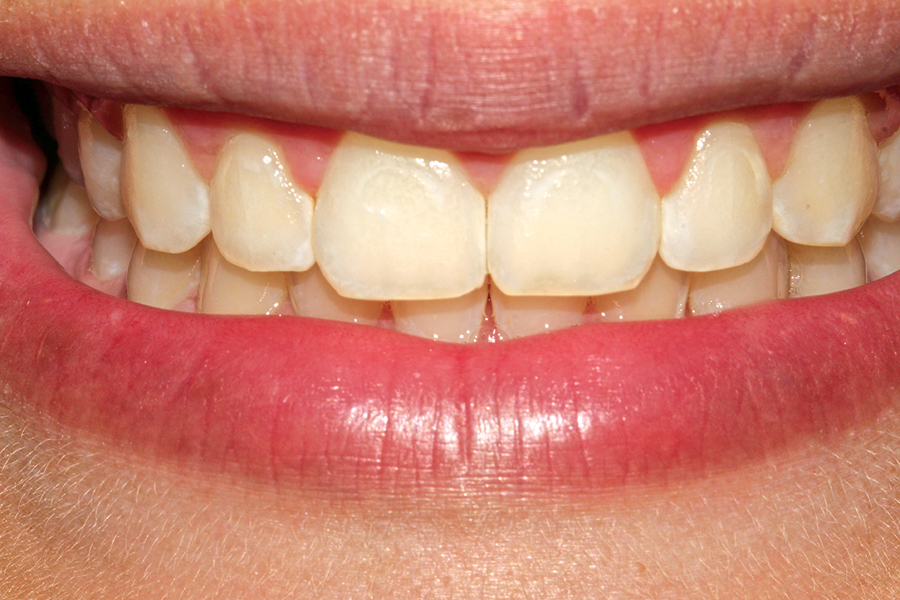

Figure B. After orthodontic treatment. Note hyperplasia of gingival secondary to anti-seizure medication

One of the foundations upon which health care professionals practice is a commitment to provide the best possible treatment to each and every one of their patients. For some patients, medical or socioeconomic circumstances may present a challenge to the delivery of optimal care. Fortunately, we live and practice in a country that provides an … Read more